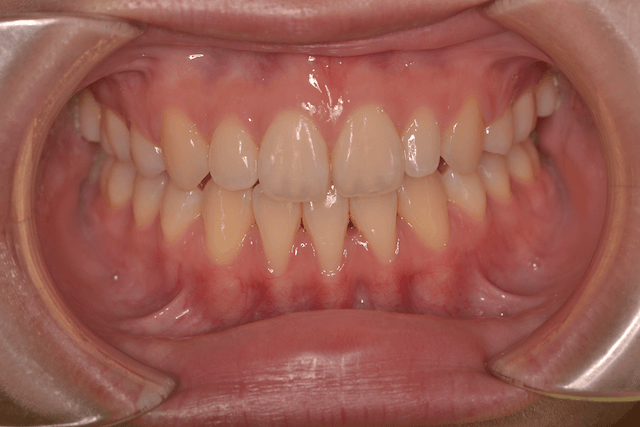

開咬(オープンバイト)を抜歯、インプラントアンカー、DBSで改善した症例

※DBSとはダイレクトボンディングシステムと呼ばれており、ブラケットにワイヤーを通して歯を動かしていく矯正治療です。

患者情報

16歳女性

主訴

前歯の隙間が気になる

行った治療内容

上顎両側4番抜歯、下顎左側1番抜歯 上顎インプラントアンカー、顎間ゴム、DBS

治療のリスク

歯根吸収、前歯部歯肉退縮

治療期間

3年6か月

※ クリックして拡大することができます。